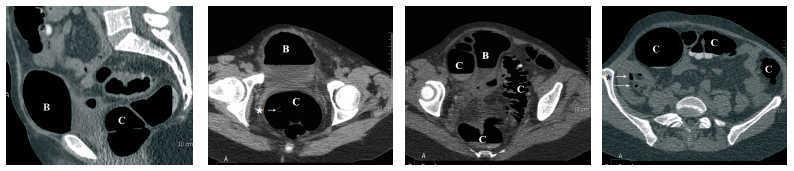

Colonoscopia limitada a 30 cm del margen anal por angulación del colon. Diverticulosis. La colonoscopia virtual realizada (reconstrucción TAC) ofrece el diagnóstico final de fístula colovesical.

Figura .